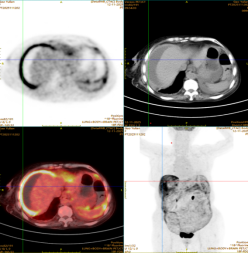

外院曾行诊断性腹腔穿刺,却未能明确病因。PET-CT 检查提示恶性肿瘤可能。为寻求进一步诊治,家属来到医院胃肠甲状腺外科找到杨战锋主任。

另一位 80 岁老年女性患者因精神萎靡、低热就诊,腹部 CT 检查发现其腹腔积液分布颇具特征:肝脏边缘呈「扇贝形」受压,大网膜增厚呈「饼状」。外院治疗效果不佳,遂至郑大五附院求诊。